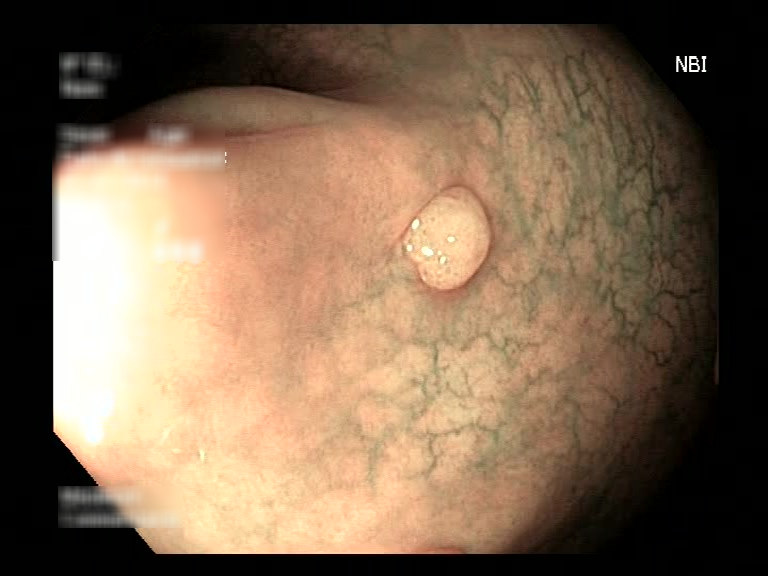

| Lesion | White Light Frame | NBI Frame | White Light Video | NBI Video | Camera Calibration |

| hyperplasic_01 |  |

|

WL.mp4 | NBI.mp4 | cam.xml |